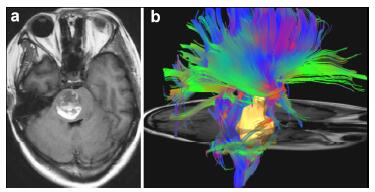

MRI is the most necessary examination for BSCMs in terms of diagnosis and differential diagnosis. CTA and DSA play important roles in distinguishing CMs with AVMs. Because of hemorrhage, typical imaging appearances of BSCMs are hyperintense core (methemoglobin) surrounded by hypointense rim (hemosiderin) on both T1-and T2-weighted MRI (Figure 1). Gradient-echo scan, especially susceptibility weighted imaging (SWI), can be used to find small occult lesions. CTA or DSA generally failed to reveal the BSCMs because of lacking feeding arteries.

| Figure 1 MRI demonstrated the typical "porpcorn" or "mulberry-like" BSCMs. (a), (b) and (c) showed one patient with pontine cavernoma. (d), (e) and (f) showed another patient with left cerebellar peduncle cavernoma. (a) and (d) axial T1-weighted, (b) and (e) axial T2-weighted, (c) axial enhanced T1-weighted, (f) SWI. |